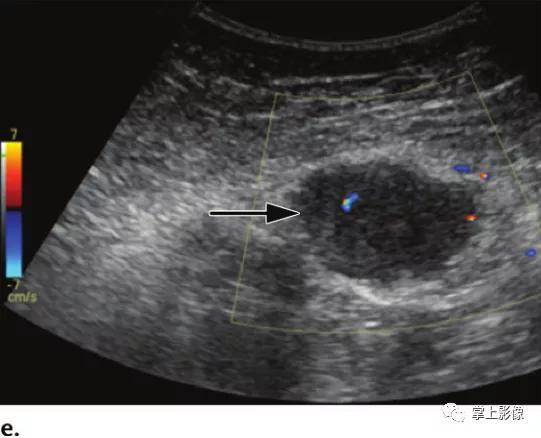

35岁女性腹壁硬纤维样瘤,经皮穿刺活检证实。(A)轴位CT显示以左直肌鞘为中心的高强化腹壁肿块(箭头)。(b-d)轴位平扫T1WI显示低信号肿块。注射钆对比剂后,在动脉期(C)、门静脉期(未显示)和延迟期(D)图像上可见肿块(b-d箭头)渐进性均匀强化。(E)超声图像显示低血流低回声肿块(箭头)